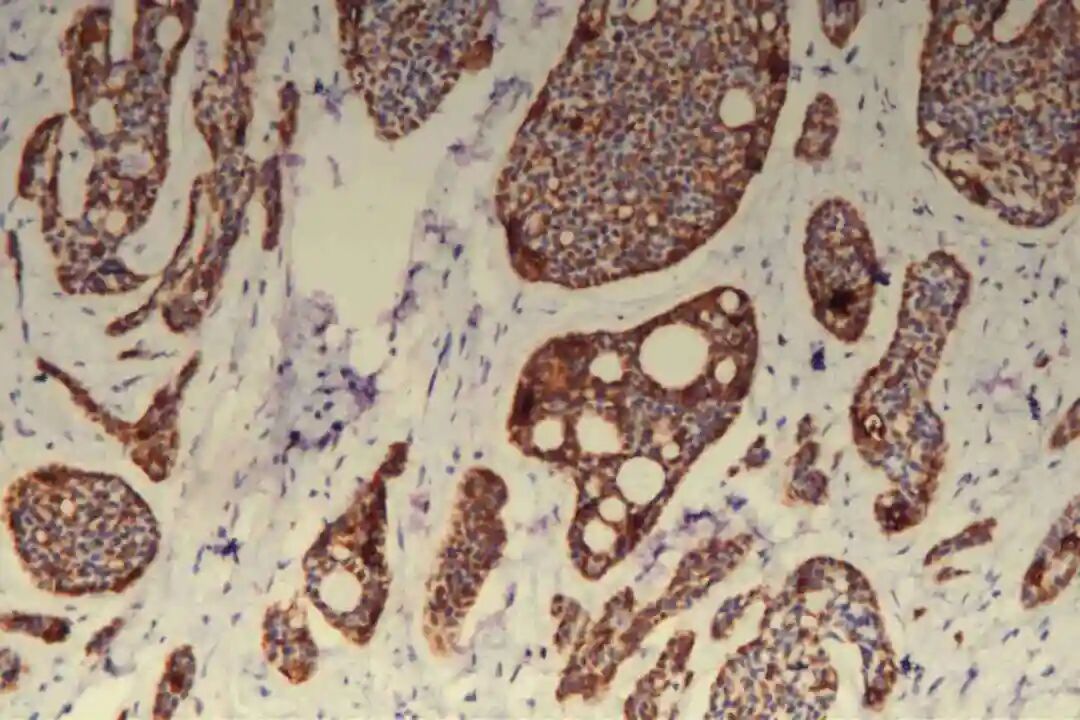

腺上皮细胞主要表达细胞角蛋白(CK)家族相关标志物,其中CK7、CK8/18呈弥漫阳性表达,CK19呈局灶性阳性表达,这是确认腺上皮细胞来源的核心依据;部分病例中,腺上皮细胞可表达CD117(c-Kit),呈弥漫或局灶阳性,CD117在实体型区域的阳性表达率高于经典型区域,可作为实体型PACC的辅助鉴别指标。此外,腺上皮细胞不表达雌激素受体(ER)、孕激素受体(PR)及人表皮生长因子受体2(Her-2),即“三阴性”表型,这是PACC与激素受体阳性乳腺癌、Her-2阳性乳腺癌的重要区别,也是临床治疗方案选择的重要依据之一。

免疫组化:09号片:ER(-),PR(-),Her-2(2+),CK7(腺上皮+),CD117(+),CK5/6(肌上皮+),P63(肌上皮+),GCDFP-15(-),GATA3(-),S-100(+,显示神经侵犯),P120(膜+),E-Cadherin(膜+),P53(野生表型),Ki67(+)10%。